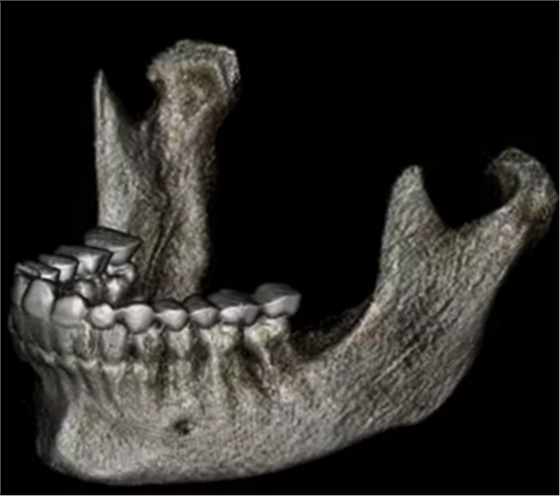

在輸出的3D模型上,使用體內(nèi)軟件(Anatomage,San Jose,Calif)將下頜骨以最小的間隔從顱骨上分離(圖5)用于保留下頜骨的咬合細節(jié),游離的下頜骨被保存(圖6,A)。同時,將沒有下頜骨的顱骨導出并保存(圖6,B)。

圖6. A,從整個3D模型上修剪的下頜骨; B,修剪的顱骨。